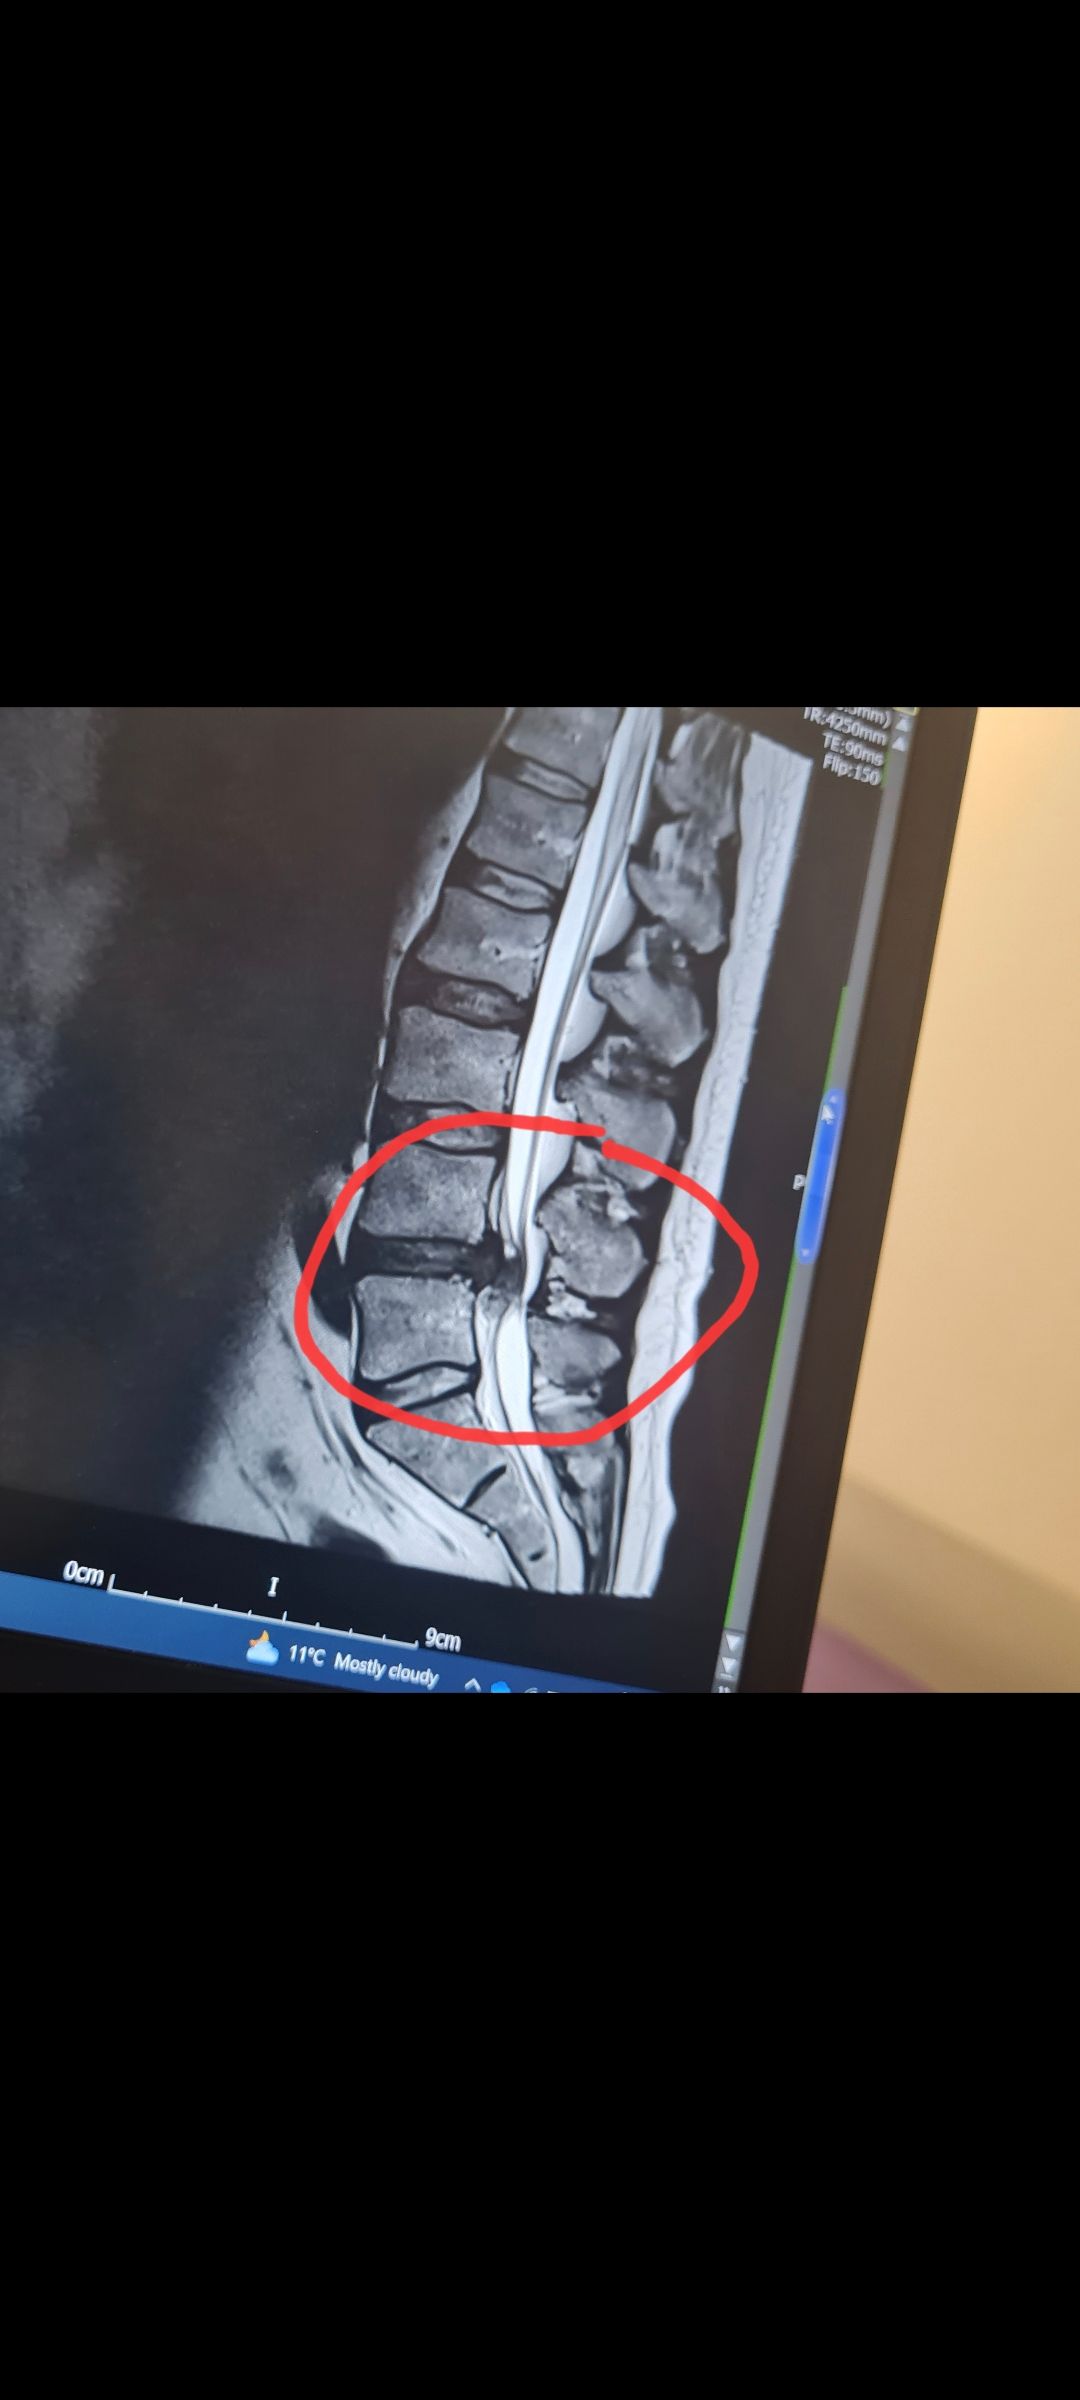

Disks L4 and L5 if that matters to anyone.